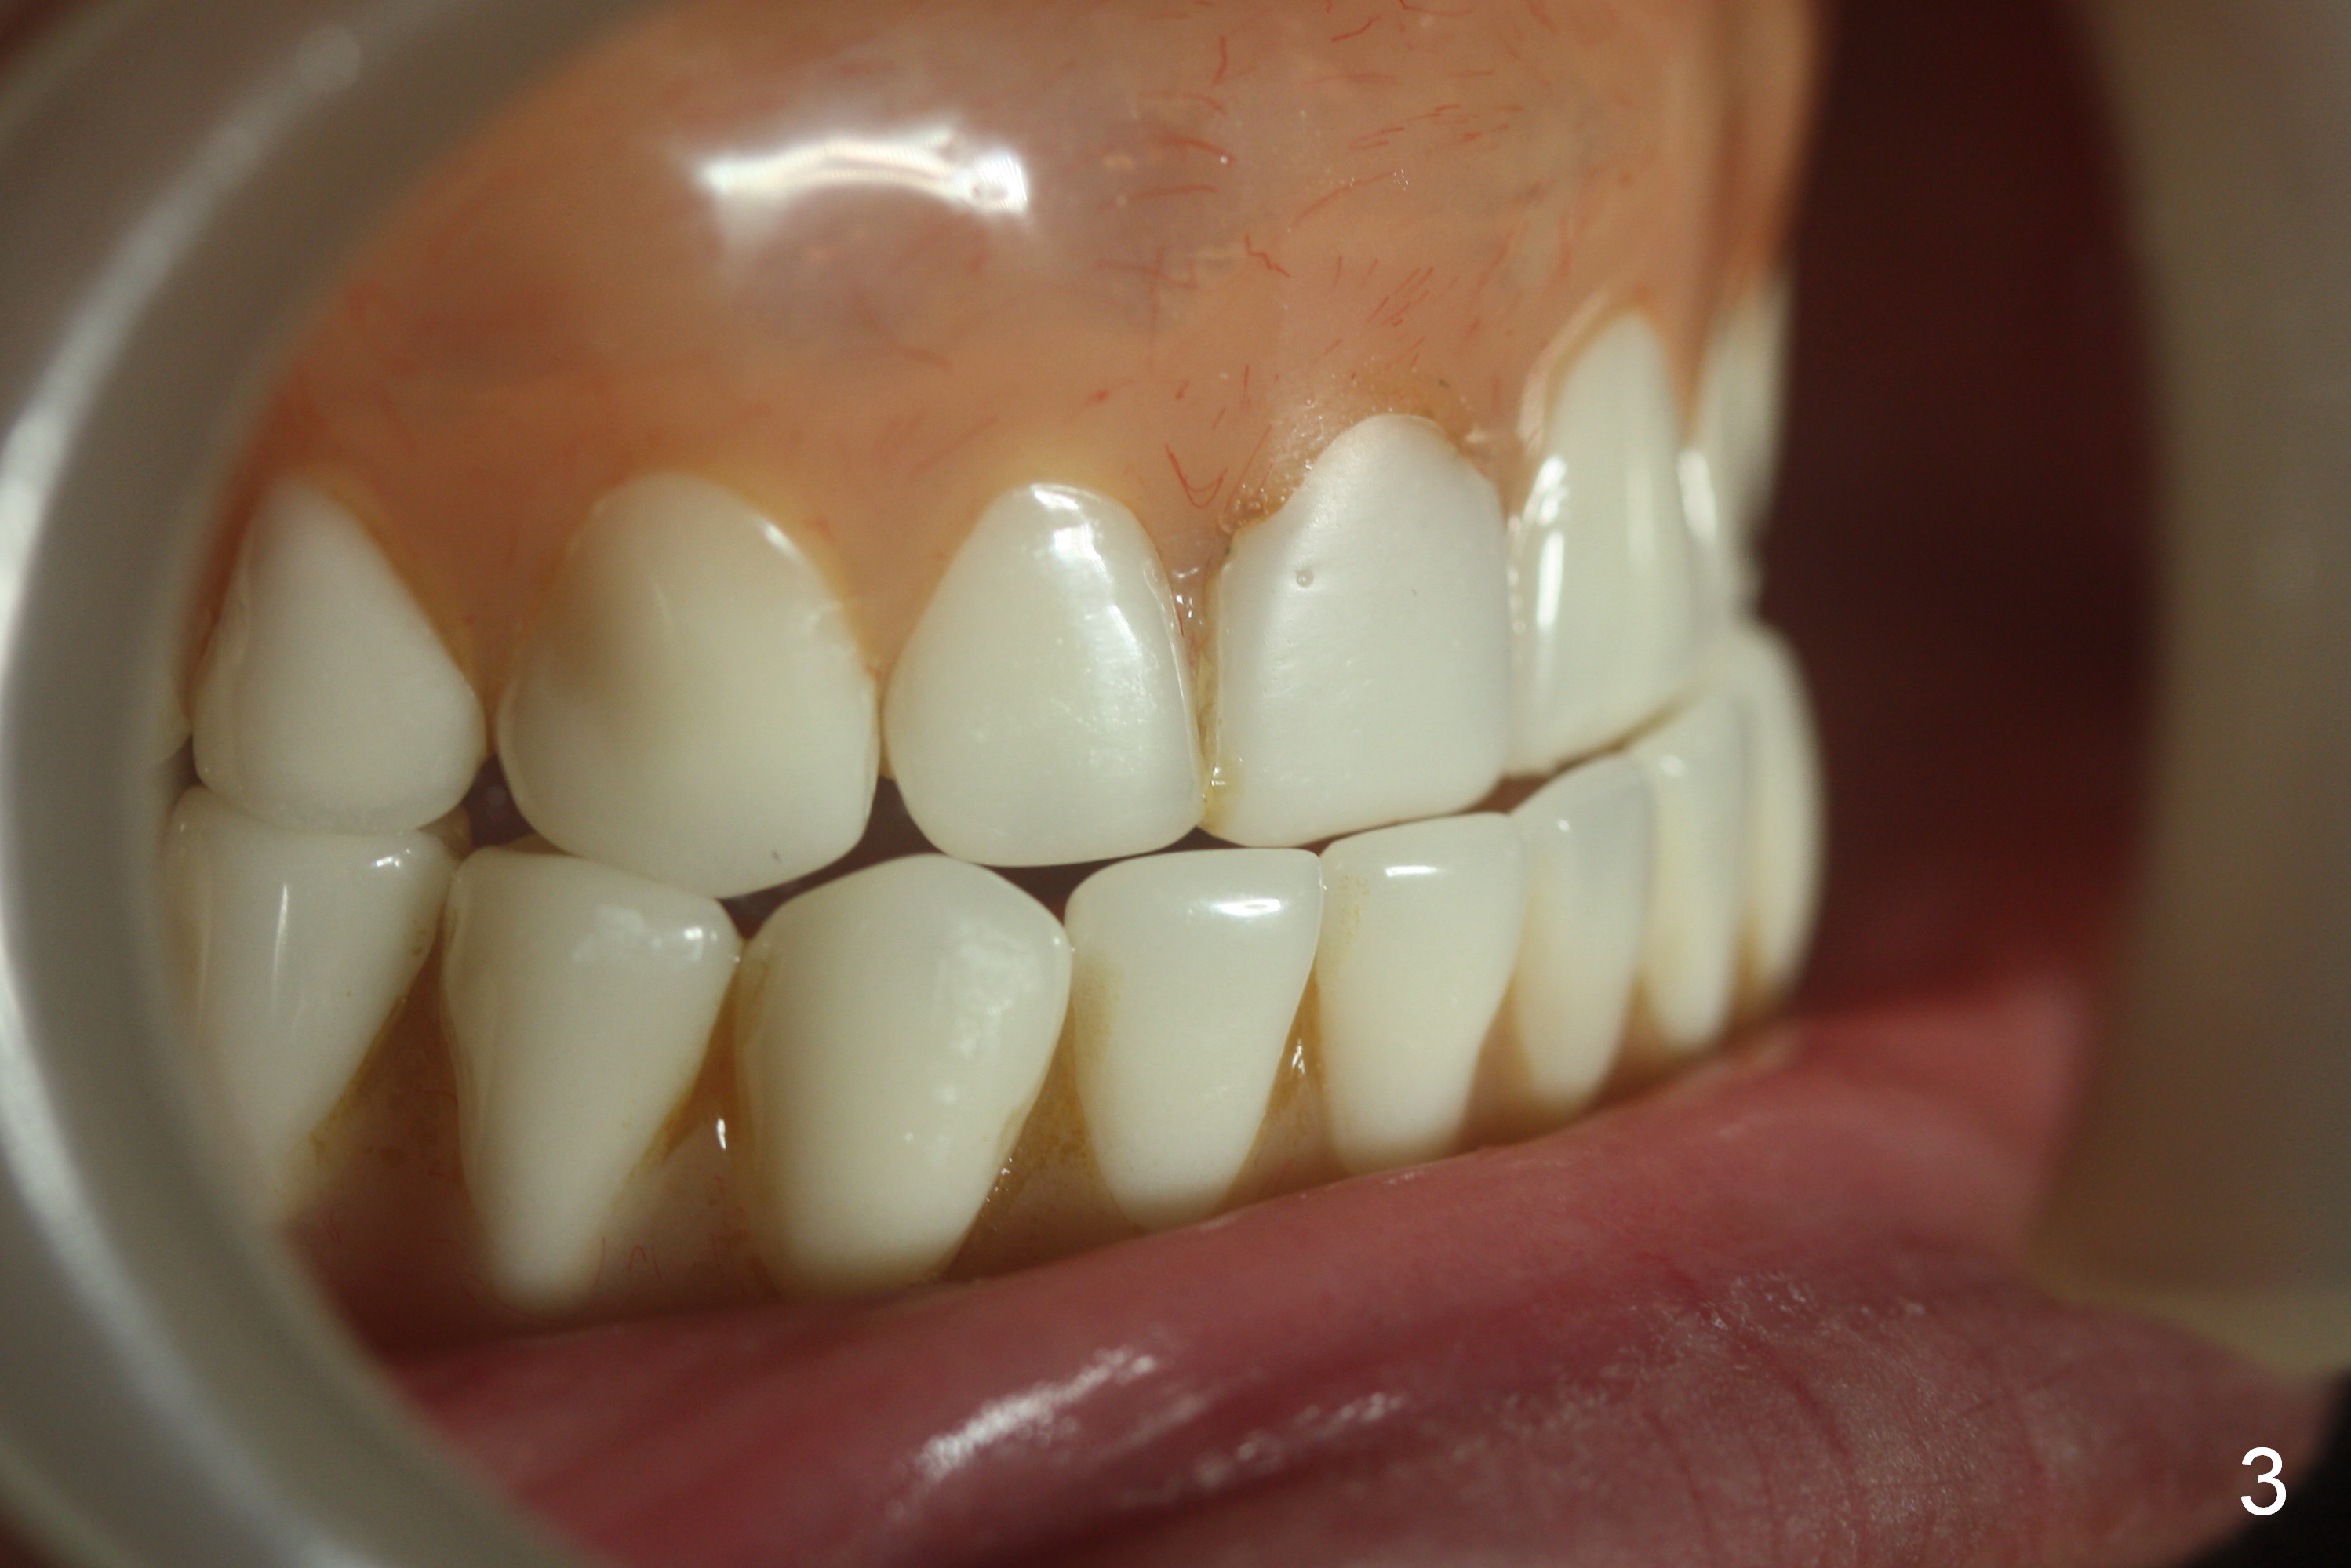

Preop photo shows that the lower lip is protrusive (Fig.1), because the lower complete denture (CD) is in cross bite (Fig.3). When the upper and lower CDs are removed, the upper and lower lips are retrusive (Fig.2). Use a modified CT scan stent to start osteotomies at the sites of the canine and the 1st premolar (Fig.4). In fact the right ones are more distal than planned. As expected, four of 3.8x8 mm implants are placed with insertion of 3.9 mm ball abutments with 2 mm cuff (Fig.5). The lingual plate at the site of #21 perforates apically when a 2.7 mm drill is being used. The defect is repaired with collagen plug and autogenous bone and Osteogen prior to implant placement. There is no postop sublingual edema or paresthesia. With trimming of the lower CD (especially the posterior border), the four implants/ball abutments appear to help establish normal overjet with immediate improvement of the facial profile (Fig.6,7 (3 days postop)). The border of the denture flange is trimmed (Fig.7 black *) to avoid contacting the tender hyperplastic tissue (white *). Further trimming may be necessary, which has been accomplished. A month later, three more implants are placed in the mandible.